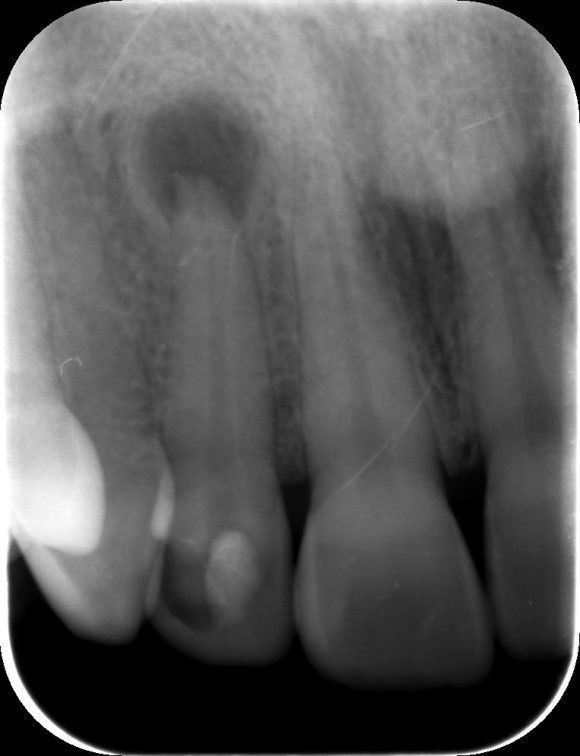

Így derülhet ki, hogy van-e cisztád

Általában egy alapos fogászati szűrővizsgálat vagy egy góckutatás során szerzünk tudomást a szájüregi ciszta létezéséről, hiszen ezek a képletek nagyon jól kivehetőek a panoráma röntgen felvételeken. Kezdetben a ciszta tünetmentes lehet, de később már mi magunk is tapasztalhatjuk a kellemetlenségét.

Gyökércsúcsi ciszta keletkezése

1. A baktériumok, a beteg fog gyökerén át a gyökércsúcson keresztül kijutnak a csontba, ott pedig gyulladást idéznek elő.

2. Az itt megrekedt hámsejtek szaporodásával kialakul a ciszta tömlője.

3. A cisztában folyadék termelődik, s a növekvő hólyag nyomást idéz elő a csontban, ami pedig lassanként visszahúzódik, felszívódik.

4. A ciszta folyamatosan növekszik, idővel akár a csontfal is kidudorodhat.